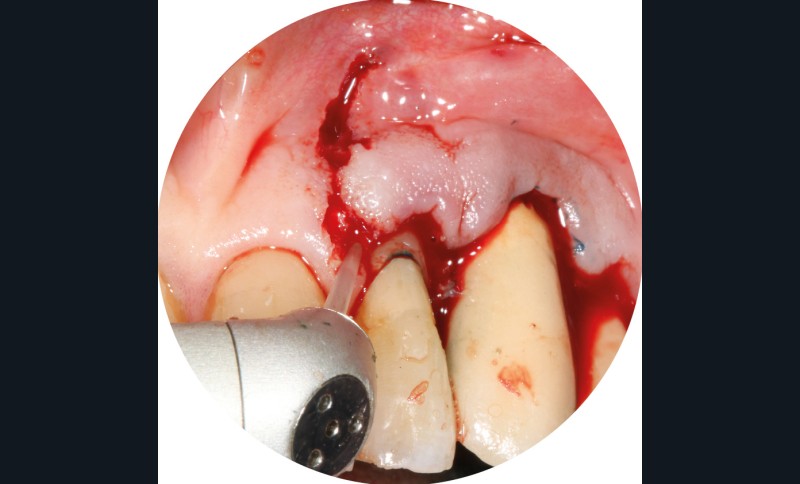

– Le laser Er-YAG, utilisé pour le nettoyage, est un laser avec un milieu actif composé d’yttrium, d’aluminium et de grenat dopé à l’erbium. Avec une longueur d’onde de 2 940 nm situé dans l’infrarouge, le laser Er-YAG est un laser à haute énergie, dont la lumière est absorbée dans l’eau et dans l’hydroxyapatite et qui ne pénètre pas profondément. Ceci permet de couper des tissus mous et des tissus durs, mais également de désorganiser le biofilm bactérie.

C’est un laser idéal pour le traitement chirurgical des péri-implantites. Il permet l’élimination du tissu de granulation à la surface de l’implant et de l’os ainsi qu’une décontamination mécanique par effet photoablatif.– Le laser Diode, utilisé pour la décontamination…